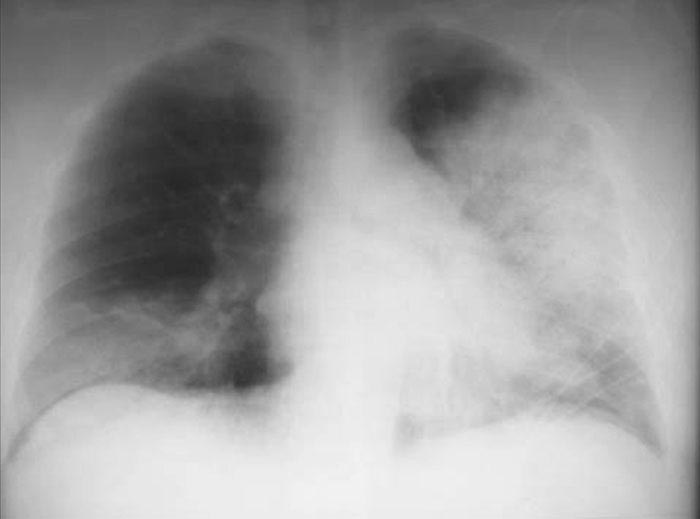

Corticoides en la neumonía severa

23 enero 2018

La actualización de una revisión Cochrane muestra beneficio del uso de corticosteroides en pacientes internados con neumonía severa. The Cochrane Library, 13 de diciembre de 2017